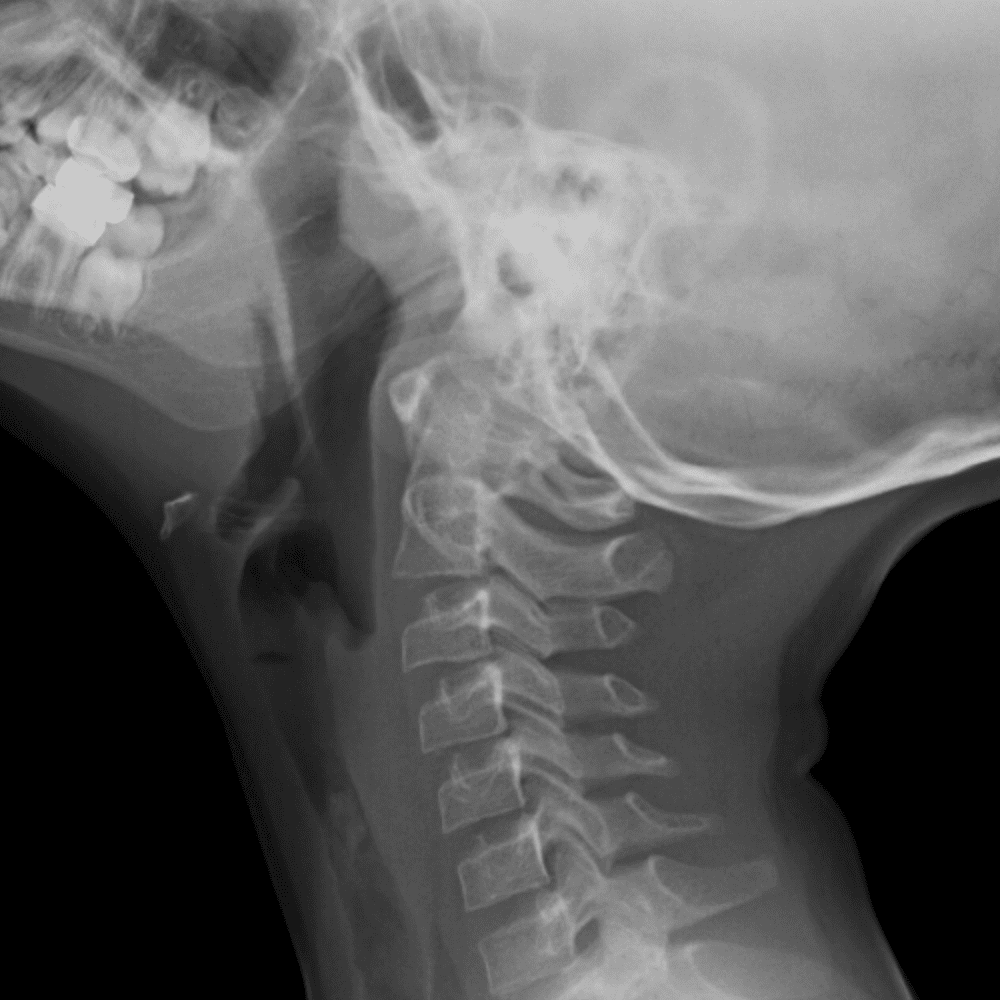

Peds Chest

Practice

Simulates call by including subtle or difficult cases and some normals.

50 cases